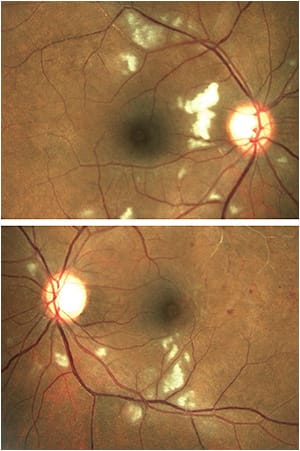

The prevalence of autoimmune diseases is staggering, affecting millions worldwide. The exact cause of autoimmunity remains unknown, although genetic and environmental factors are believed to play a role.3 One theory is that bacteria, viruses, drugs, or changes in a patient’s circumstances can trigger these immune system dysfunctions and imbalances, exacerbating the condition.3 In some cases, a change in the patient’s circumstance may worsen their condition. An example of this is the case of a 36-year-old Black female with a history of sarcoidosis in remission, which worsened during her pregnancy and caused visual symptoms associated with posterior uveitis and retinal vasculitis (Figure 1).

RA, for instance, may lead to scleritis, episcleritis, or dry eye disease. Sjögren’s syndrome, characterized by lymphocytic infiltration of exocrine glands, commonly causes dry eye disease and keratoconjunctivitis sicca. SLE, a connective tissue disease, can alter the connective tissue of the eye, resulting in scleritis. Simultaneously, associated hematologic and vascular diseases can cause retinal hemorrhages and vaso-occlusive retinopathy (Figure 2). Similar mechanisms apply to other conditions listed in the Table on page 37.